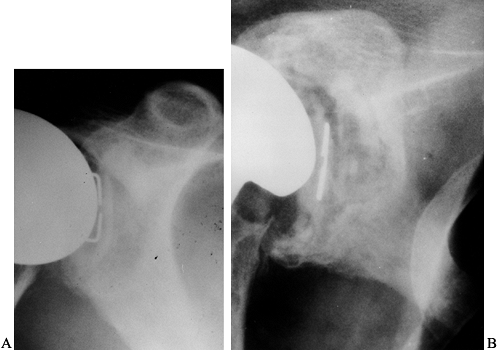

Place an antibiotic-impregnated polymethylmethacrylate cement hemiarthroplasty spacer in the humeral canal (Fig. 103.4). Palacos (Smith & Nephew Richards, Memphis, TN) is used because of its superior elution characteristics (20,34).

Figure 103.4. Anteroposterior (A) and lateral (B) radiographs of an antibiotic spacer placed after removal of an infected prosthesis. -